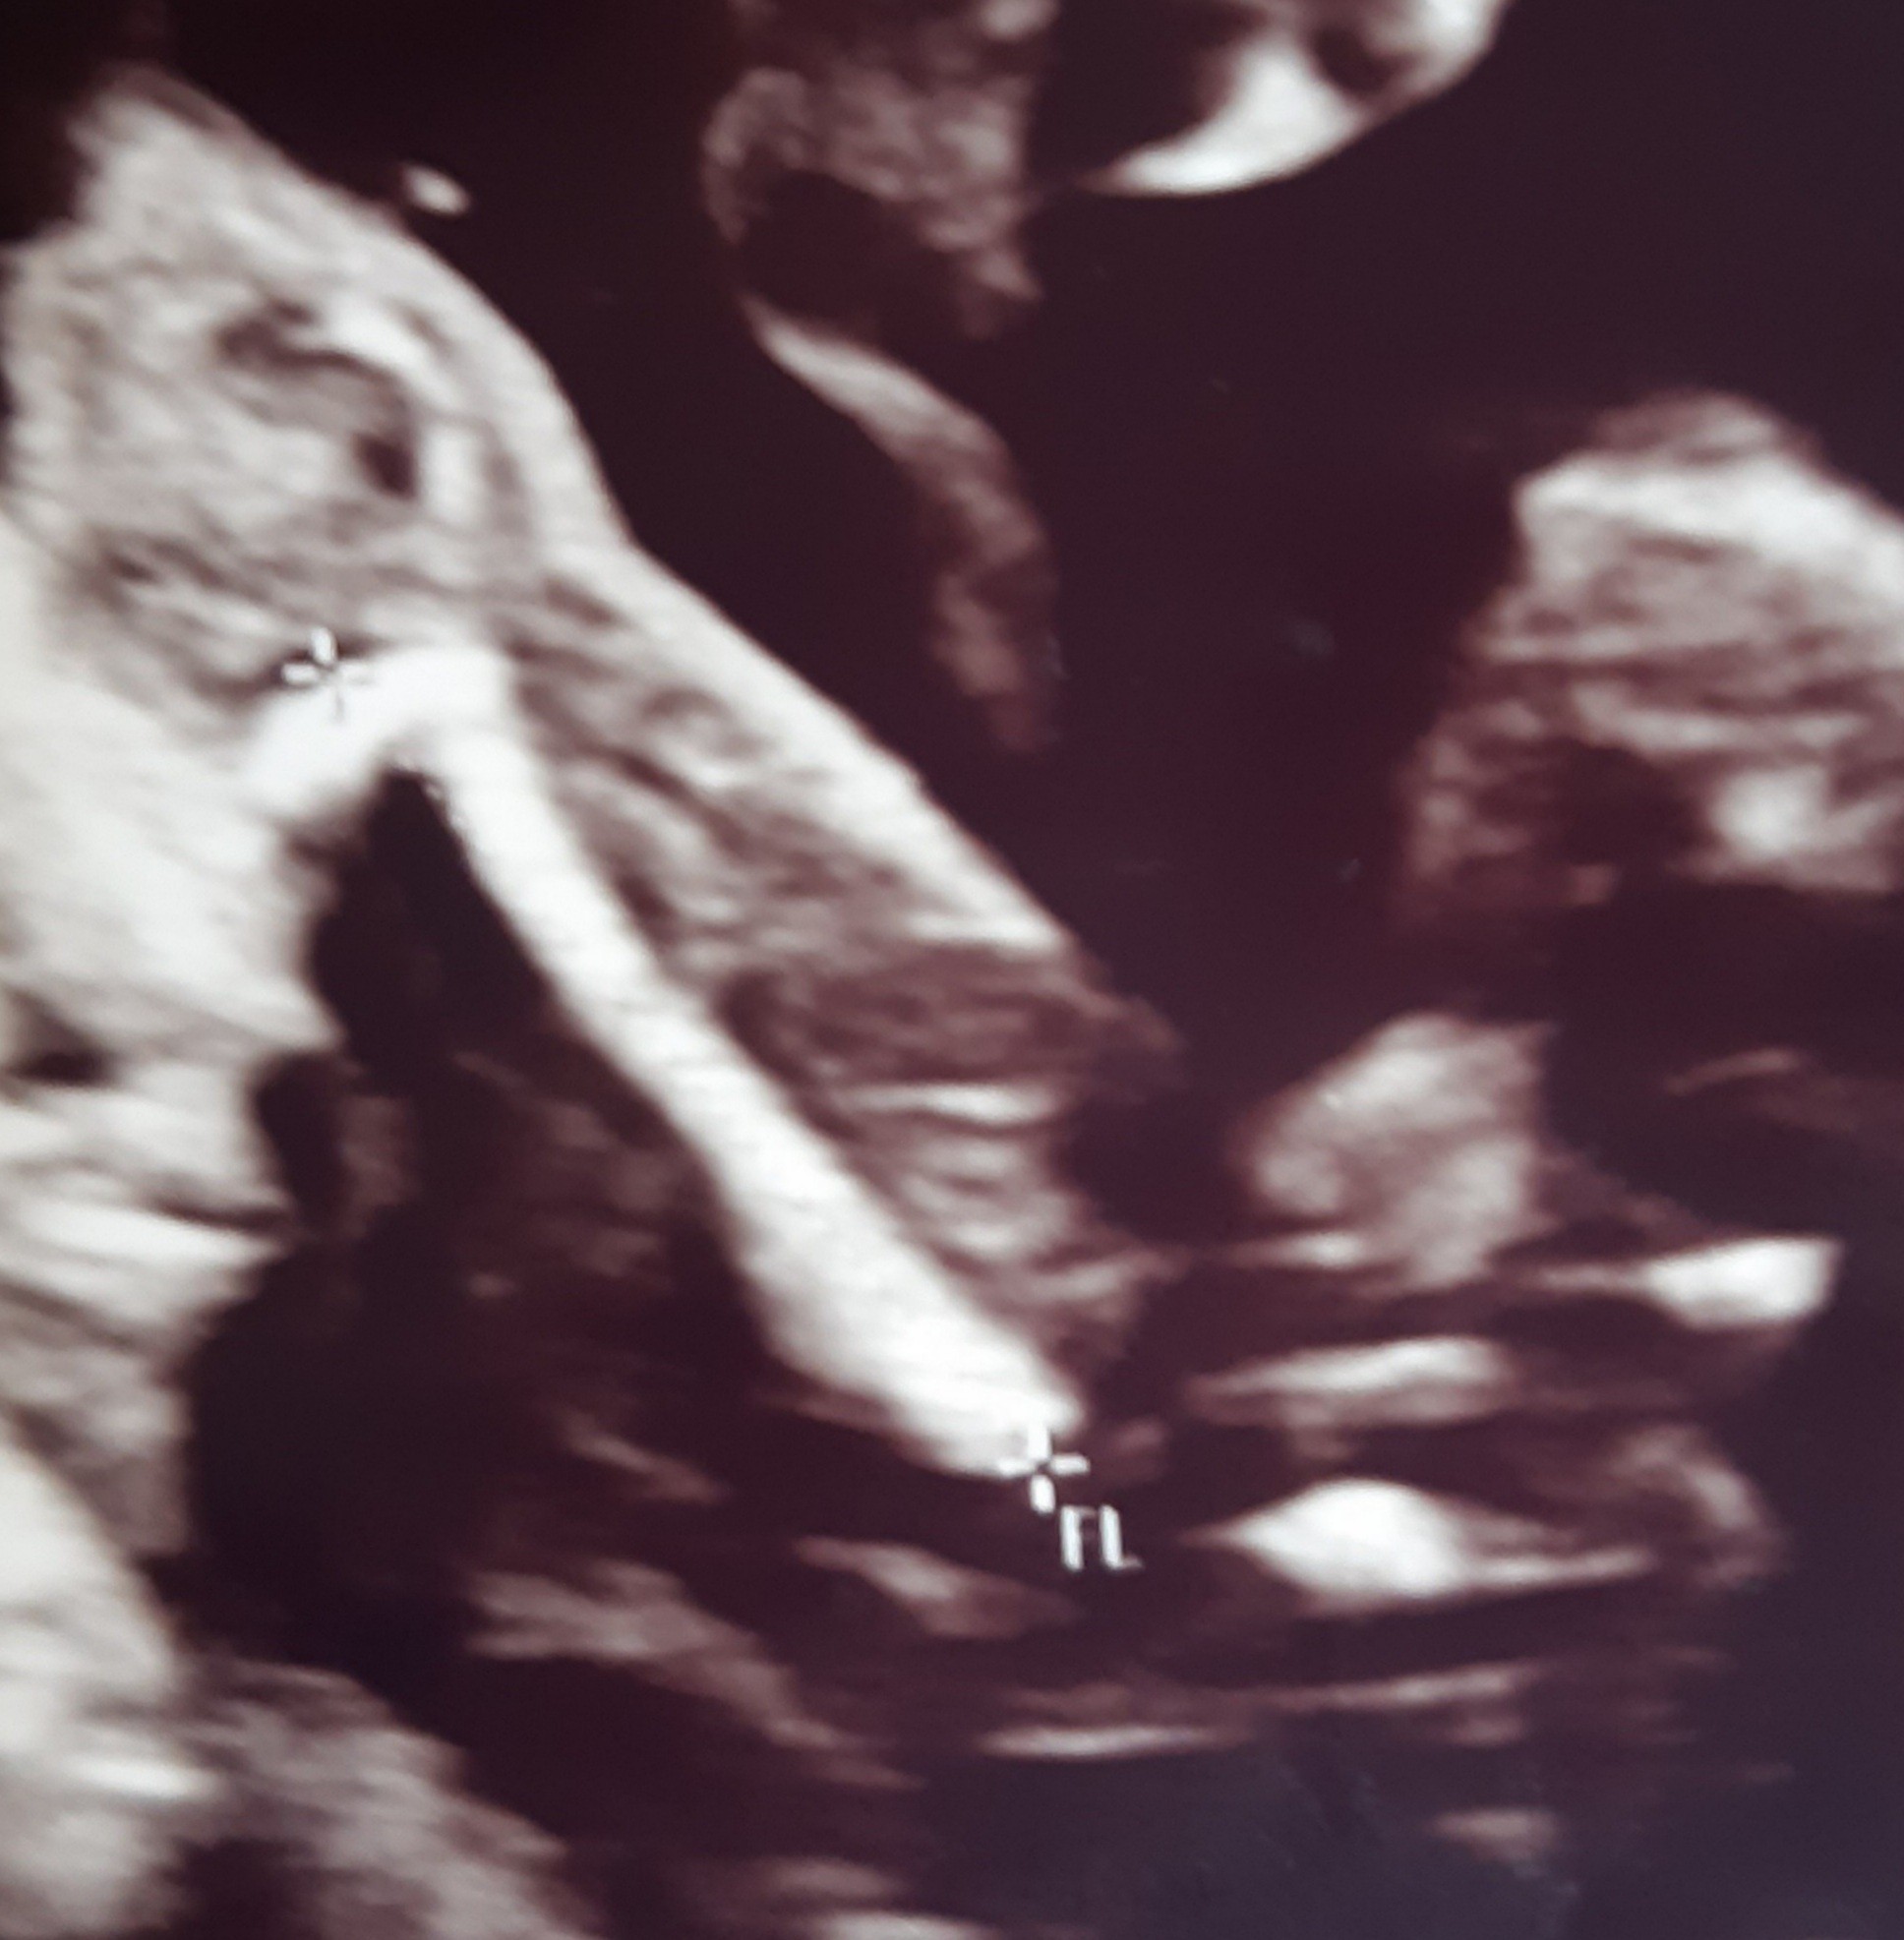

Dziewczynka.Mam pytanie jak uważacie dziewczynka czy chłopiec.

Może któraś miała podobne usg. PomocyZobacz załącznik 1138906